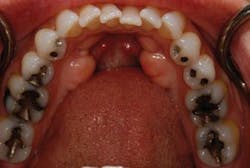

Full arch, occlusal images, as part of a photographic series, are an important adjunct to the new-patient examination. Images of only one or two teeth, such as those commonly captured with an intraoral camera, center on single-tooth dentistry but do little to help clinicians, staff, or patients think about patient needs in a comprehensive fashion (Fig. 1). The way clinicians evaluate and communicate with patients should be in alignment with the way they wish to treat their patients. Patients can better understand their needs when they can clearly see the "big picture." Full arch, occlusal images are an excellent way to help patients see the big picture and should be part of any new-patient examination (Figs. 2 and 3).

For instance, many patients, when given the option, may prefer to combine both immediate-need treatment with future-need treatment. Advantages of this approach include decreased chair time and fewer visits, impressions, and injections (Fig 4). From a restorative standpoint, we can often better manage the occlusion and blending of restorative materials for an optimal result when the dentistry is approached in a more integrated way.